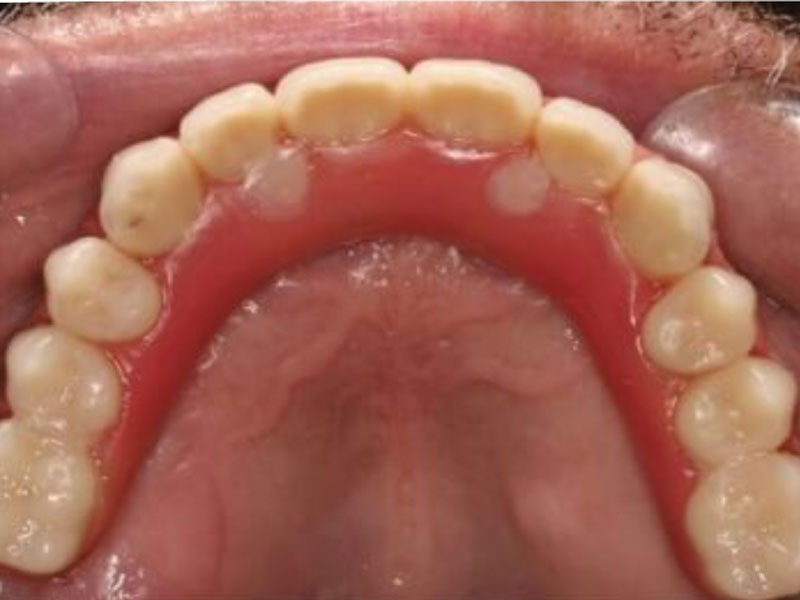

ALL ON 4 下顎 / ALL ON 6 上顎